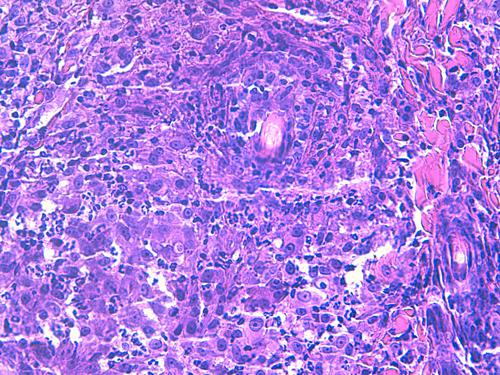

L’examen histopathologique de biopsies cutanées montre la présence d’un infiltrat dermique granulomateux de topographie périannexielle à diffuse d’intensité marquée, sans mise en évidence d’élément figuré après coloration HES, PAS et Fite-Faraco (photos 3 et 4).

cas-de-dermatite-granulomateuse-sterile-chez-chat3

Photo 3 : lésions dermiques nodulaires de topographie périannexielle

avec tendance à la coalescence, destruction

des annexes folliculaires et glandulaires.

Certains nodules sont centrés sur un espace clair. (HES, x100)